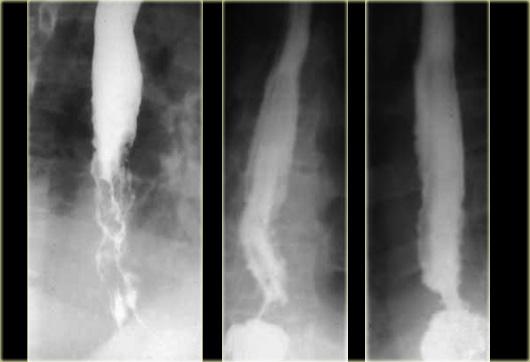

Bên trái là hình ảnh một bệnh nhân có biến chứng sau nội soi phức tạp.

Can thiệp dụng cụ gây rách niêm mạc và tụ máu trong thành thực quản dạng bóc tách, tạo ra hình ảnh lòng đôi với dải niêm mạc phân tách (các mũi tên).

Ngoài cùng bên trái là hình ảnh thoát thuốc cản quang trong thành thực quản (mũi tên) sau nong đoạn xa điều trị co thắt tâm vị.

Ở giữa là hình ảnh thoát thuốc cản quang trong thành thực quản (mũi tên) sau nội soi phức tạp.

Bên phải là hình ảnh thủng thực quản sau sinh thiết với thuốc cản quang thoát ra ngoài lòng thực quản (mũi tên).